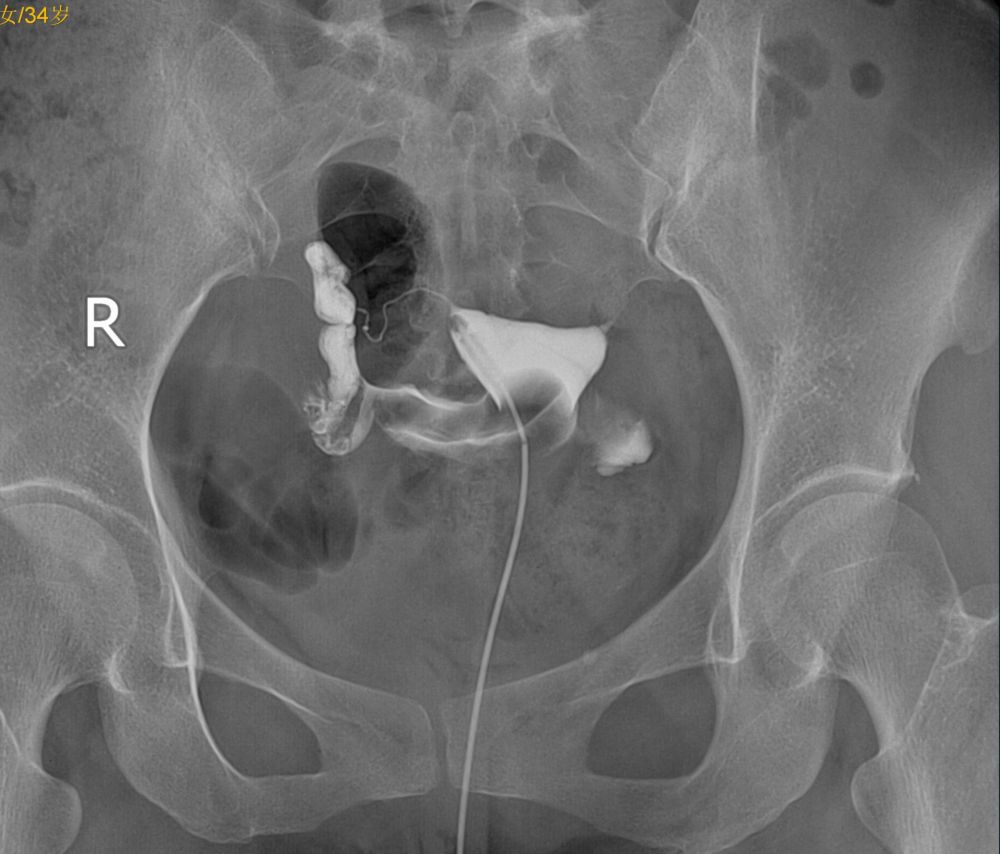

右侧输卵管通,壶腹部粗细不均,右侧宫旁静脉回流,左侧峡部不通,不是是否结扎吻合术后?

左侧输卵管峡部梗阻;右侧宫旁静脉回流。

左侧输卵管不通,右侧输卵管壶腹部粗细不均。

左侧输卵管角部梗阻,右侧宫旁静脉回流

子宫腔规整,右侧输卵管通畅,左侧输卵管阻塞。

左侧输卵管峽部梗阻,右侧宫旁静脉回流。